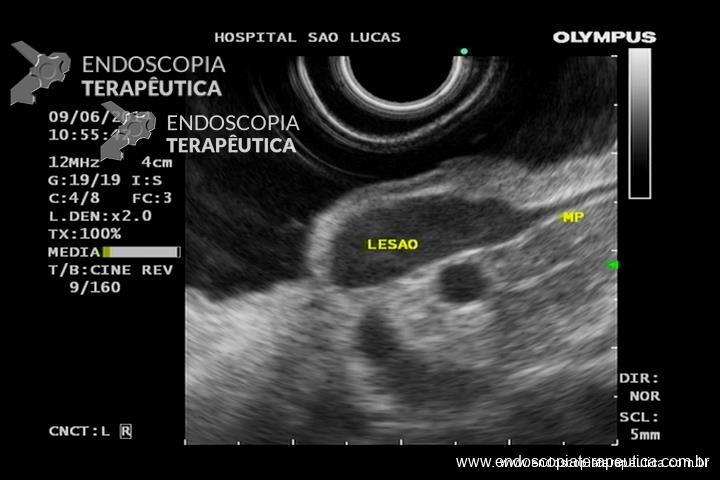

GIST gástrico